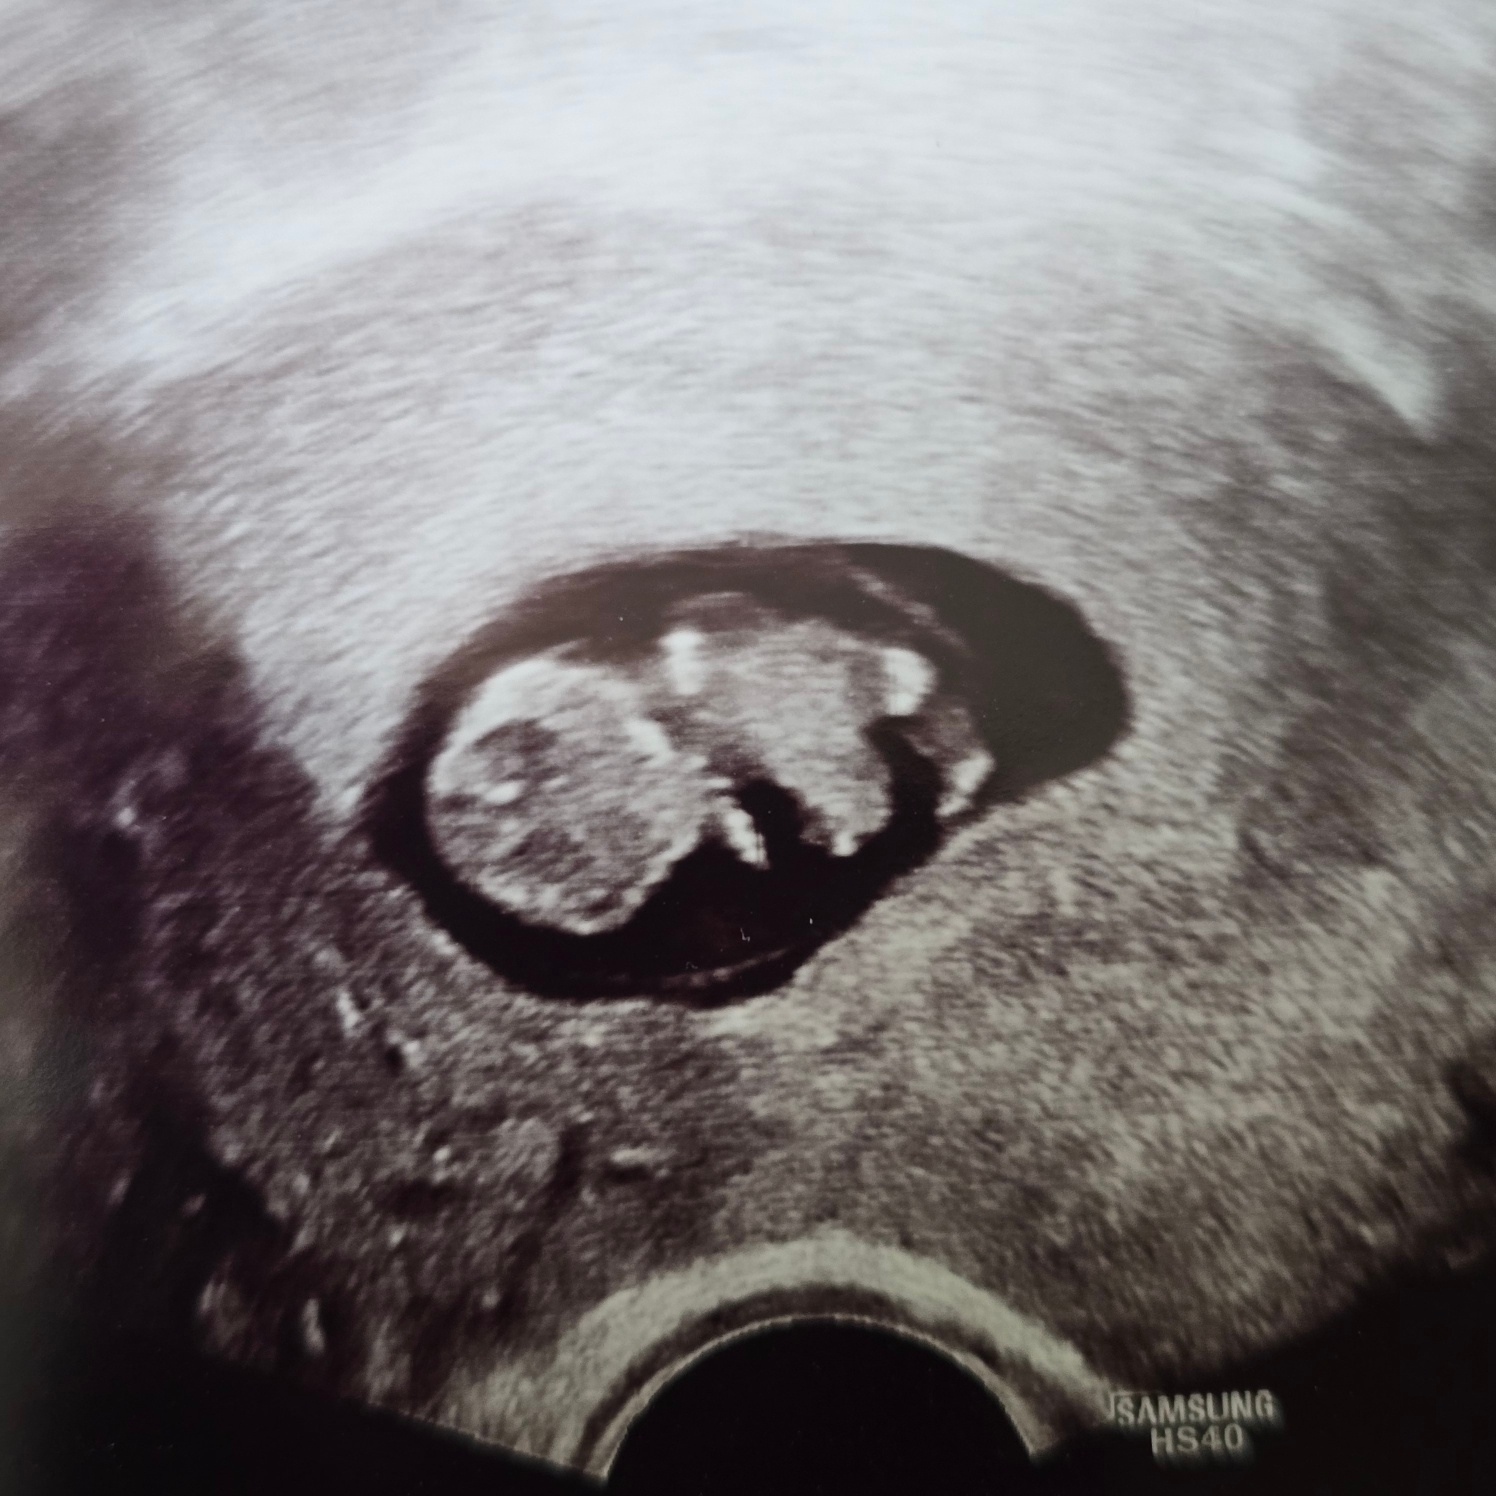

진짜? 벌써 이렇게 커졌다고?!

7주 2일엔 난황이랑 비슷한 크기였는데 7주 6일엔 난황보다 커졌다!!!

우리 뚝딱이 잘 크고 있구나~!!!

뚝딱이 크기는 7주 2일 크기로 4일 작게 꾸준히 잘 크고 있었다!!ㅎㅎ